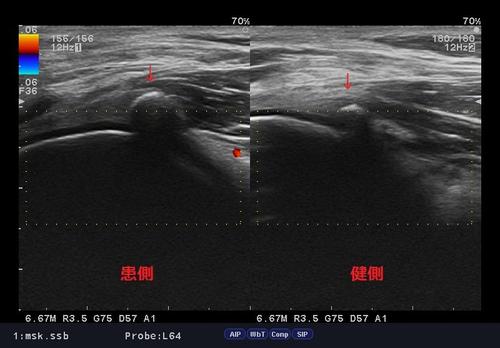

ファベラ症候群.jpg

よく問診、視診、検査を行っても半月板、靭帯損傷、関節損傷の所見はなく、

ただ膝窩外側部に限局性の圧痛、膝の伸展時痛、体重負荷時時痛が著名でした。

そこで、ある症状を疑い、エコー検査。